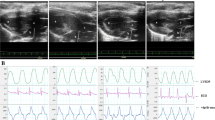

Gap junction proteins play a vital role in effective impulse propagation. Thus, we performed an electrophysiological study to assess atrial electrical changes among the groups. Figure 5A shows a schematic diagram of AF induced by burst pacing. As shown in Fig. 5F, AF inducibility was significantly higher in the DCM group than in the control group (control 16.67% vs. DCM 48.57%, P < 0.05). Although no significant differences in HRAERP, HLAERP, or LLAERP were found between the control group and the DCM group, AERPD was significantly higher in the DCM group than that in the control group (Fig. 5E). After DMB treatment, the AERPD was dramatically decreased, and AF inducibility was markedly reduced (DCM 48.57% vs. DCM + DMB 25.71%, P < 0.05), suggesting that abnormally elevated TMAO is an important cause of AF in diabetic rats.

Elevated TMAO levels increased the incidence of atrial fibrillation in diabetic rats. A Schematic diagram of the induction of AF. B HRAERP. C HLAERP. D LLAERP. E AERPD. F AF inducibility. (P < 0.05; n = 6, 6, 7, and 7 in the control, control + DMB, DCM, and DCM + DMB groups, respectively.) * P < 0.05 vs. the control group; # P < 0.05 vs. the DCM group. AF, atrial fibrillation; HRAERP, high right atrial effective refractory period; HLAERP, high left atrial effective refractory period; LLAERP, low left atrial effective refractory period; AERPD, atrial effective refractory period dispersion